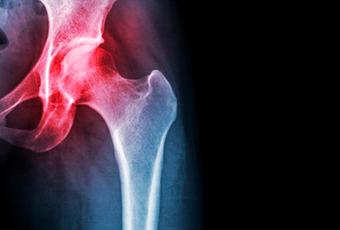

La artrosis afecta con más frecuencia a ciertas articulaciones, como son las rodillas, las vértebras y las caderas porque son las articulaciones que funcionan como puntos de apoyo sobre las que reposa el cuerpo.

Síntoma habitual de la artrosis de cadera es el dolor en el pliegue de la ingle, puede descender por la pierna y llegar hasta la rodilla. Caminar y los movimientos de rotación duelen, por ejemplo, se sufren molestias al colocarse los calcetines.